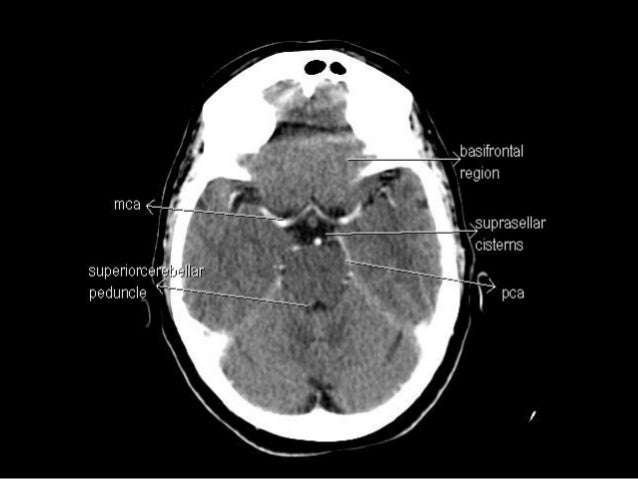

Non contrast axial ct head. The anterior part of the head is at the top of the image. Ct images of the brain are conventionally viewed from below as if looking up into the top of the head.

This means that the right side of the brain is on the left side of the viewer. Welcome to online mri ct sectional anatomy. This photo gallery presents the anatomy of the abdomen by means of ct axial coronal and sagittal reconstructions.

Online mri ct sectional anatomy kenneth k. Once the normal structures are identified abnormalities can be detected and a diagnosis may be possible. Cranial cross sectional anatomy is very important to know prior to analyzing a head ct.

Symmetry is an important concept in anatomy and is almost always present in a normal head ct unless the patient is incorrectly positioned with the head cocked at an angle. Ct brain image orientation.